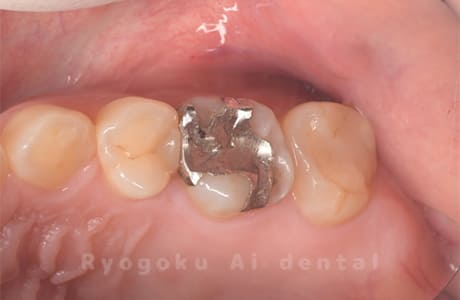

Case08

-

- 原因

- 虫歯

- 治療内容

- セラミックインレー

- 治療費用

- 77,000円

奥歯の黒い点が気になるということで来院された患者さんです。白い詰め物を外したところ、虫歯が中で大きく広がっていたため、患者さんと相談し、セラミックインレーで治療を行いました。

<リスク・副作用>

過度の咬合や衝撃で割れることがあります。